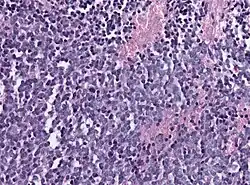

Histology of pineoblastoma

Biopsy is required for diagnosis. Pineoblastomas appear as high grade, highly cellular, small blue cells histologically. Features of aggressive malignancies can be seen, like high nucleus-to-cytoplasm ration, poorly differentiated cells, high mitotic activity, and necrosis.[13][3] Homer Wright, or neuroblastic, and Flexner-Wintersteiner, or retinoblastic, rosettes can also be seen. In contrast to other masses of the pineal gland, pineocytomatous rosettes are not present.[13] Immunohistochemistry staining will reveal neuronal, glial, and photoreceptor marker positivity. This includes synaptophysin, neurofilament protein, and CRX, a specific pineal or retinal marker, positive staining.[13][7] Four methylation-based subtypes of pineoblastoma with clinical relevance is now recognized.[15]